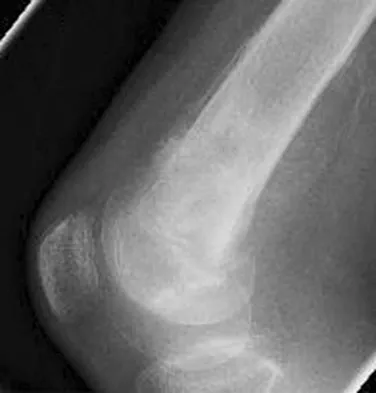

A 45-year-old male karate instructor sustained the injury shown in Figures 40a through 40c while practicing karate. The decision to proceed with surgery depends on which of the following factors?

Explanation

The most important criteria in determining the need for surgery following a nondisplaced or minimally displaced tibial plateau fracture is knee stability to varus/valgus stress. Soft-tissue injury noted on MRI may be addressed at a later time following fracture healing. This fracture pattern is amenable to nonsurgical management. Decisions regarding surgical intervention may be made up to 2 weeks after injury.